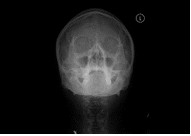

胸部、腹部をはじめ、頭部、椎体(頚椎・胸椎・腰椎)、骨盤、四肢など、全身の骨の撮影を行います。X線を用いて痛みを感じることなく、体の中の様子を調べることができる検査です。病変や骨折などを診断しやすくするため、いろいろな体位、方向から撮影します。 読影(画像診断)は日本放射線学会で認定されている経験豊富な放射線専門医が担当しています。

| 胸部 | 腹部 | 頭 |